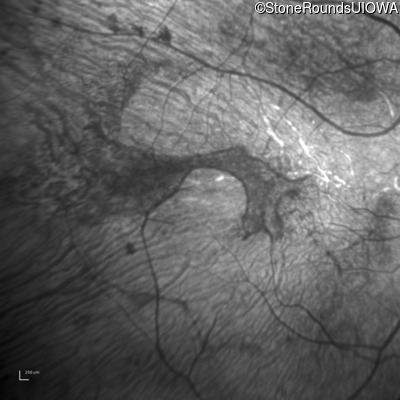

This 30 year old woman has had poor vision in her right eye for her entire life and first noticed decreased vision in dim light and constricted fields in her left eye in middle school. She had surgery in infancy for "short gut syndrome" and had liver transplantation at age 3. She also has a history of pulmonary stenosis, scoliosis, and ataxia.